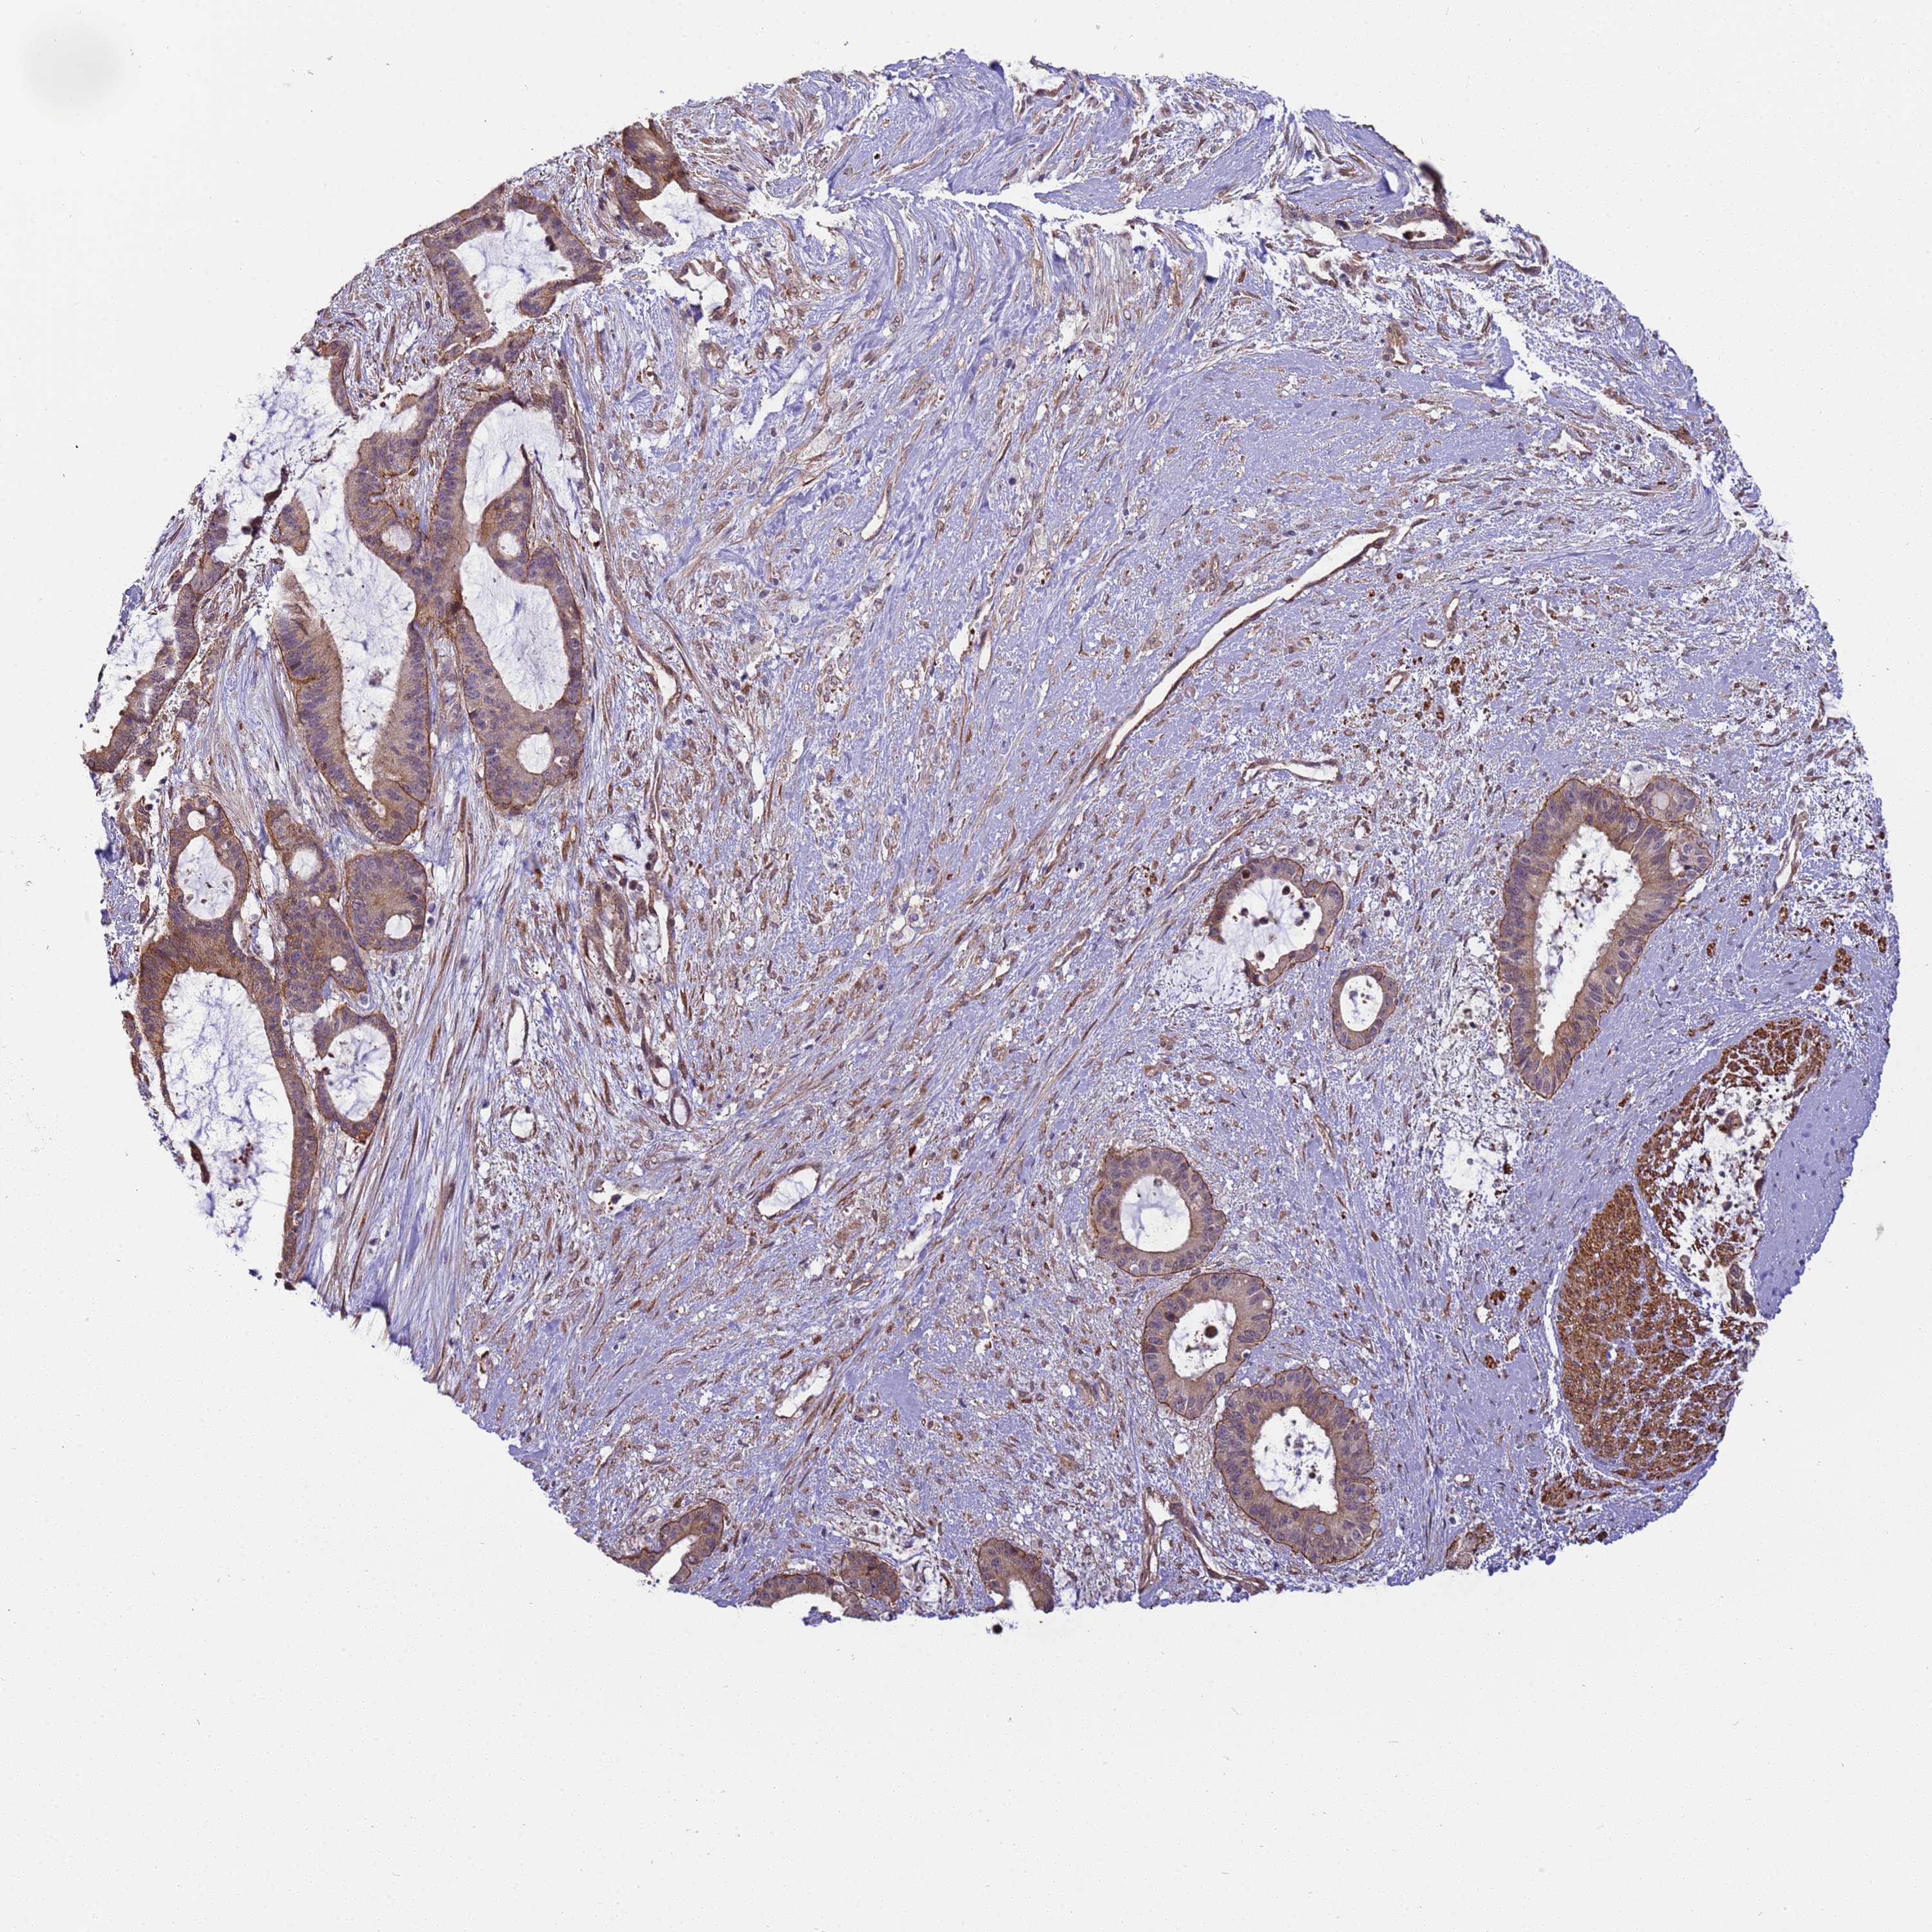

LIVER CANCER - Protein expressioni

A mouse-over function shows sample information and annotation data. Click on an image to view it in a full screen mode. Samples can be filtered based on level of antibody staining by selecting one or several of the following categories: high, medium, low and not detected. The assay and annotation is described here.

Note that samples used for immunohistochemistry by the Human Protein Atlas do not correspond to samples in the TCGA dataset.

Antibody stainingi

Antibody staining in the annotated cell types in the current human tissue is reported as not detected, low, medium, or high, based on conventional immunohistochemistry profiling in selected tissues. This score is based on the combination of the staining intensity and fraction of stained cells.

Each image is clickable and will lead to virtual microscopy that enables deeper exploration of all samples and also displays staining intensity scores, fraction scores and subcellular localization as well as patient and tissue information for each sample.

Antibody HPA036348

Antibody HPA036349

Antibody CAB002422

Antibody CAB005258

Cholangiocarcinoma

Carcinoma, Hepatocellular, NOS